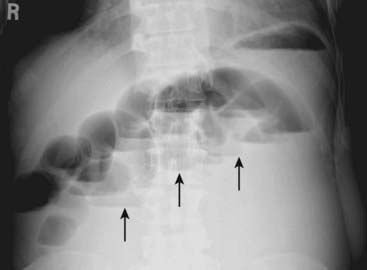

Figure 14-2 Generalized adynamic ileus, supine (A) and upright abdomen (B).

There are dilated loops of large (solid white arrows) and small bowel (dotted white arrows) with gas seen down to and including the rectum (solid black arrows). The patient had undergone colon surgery the previous day.